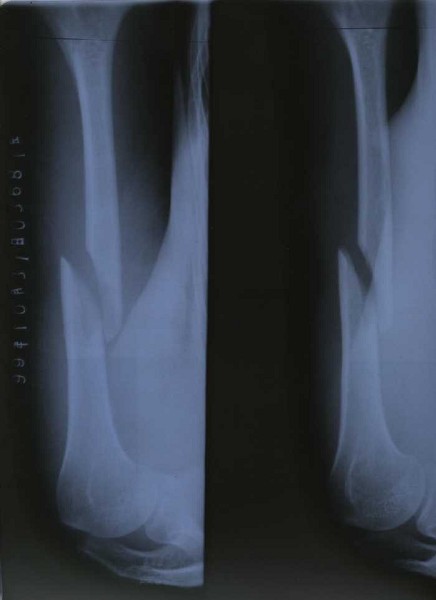

1999年,浙江省海鹽縣項進英於被警察打至骨折

|